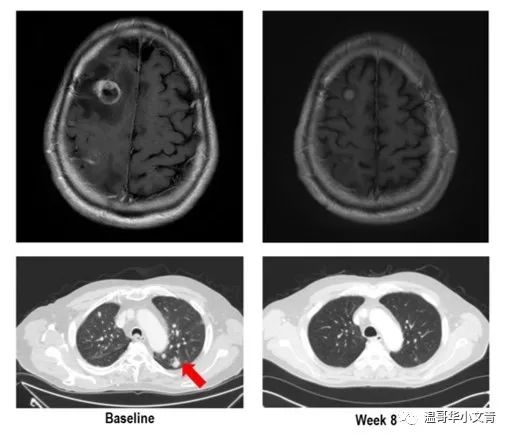

这图是一个73岁有RET基因融合的未分化型甲状腺癌病人,经历了手术,放疗,化疗之后,病灶仍然转移到了脑部。服用了LOXO-292八周后,脑部和肺部的转移灶明显减小。惊不惊喜?意不意外?